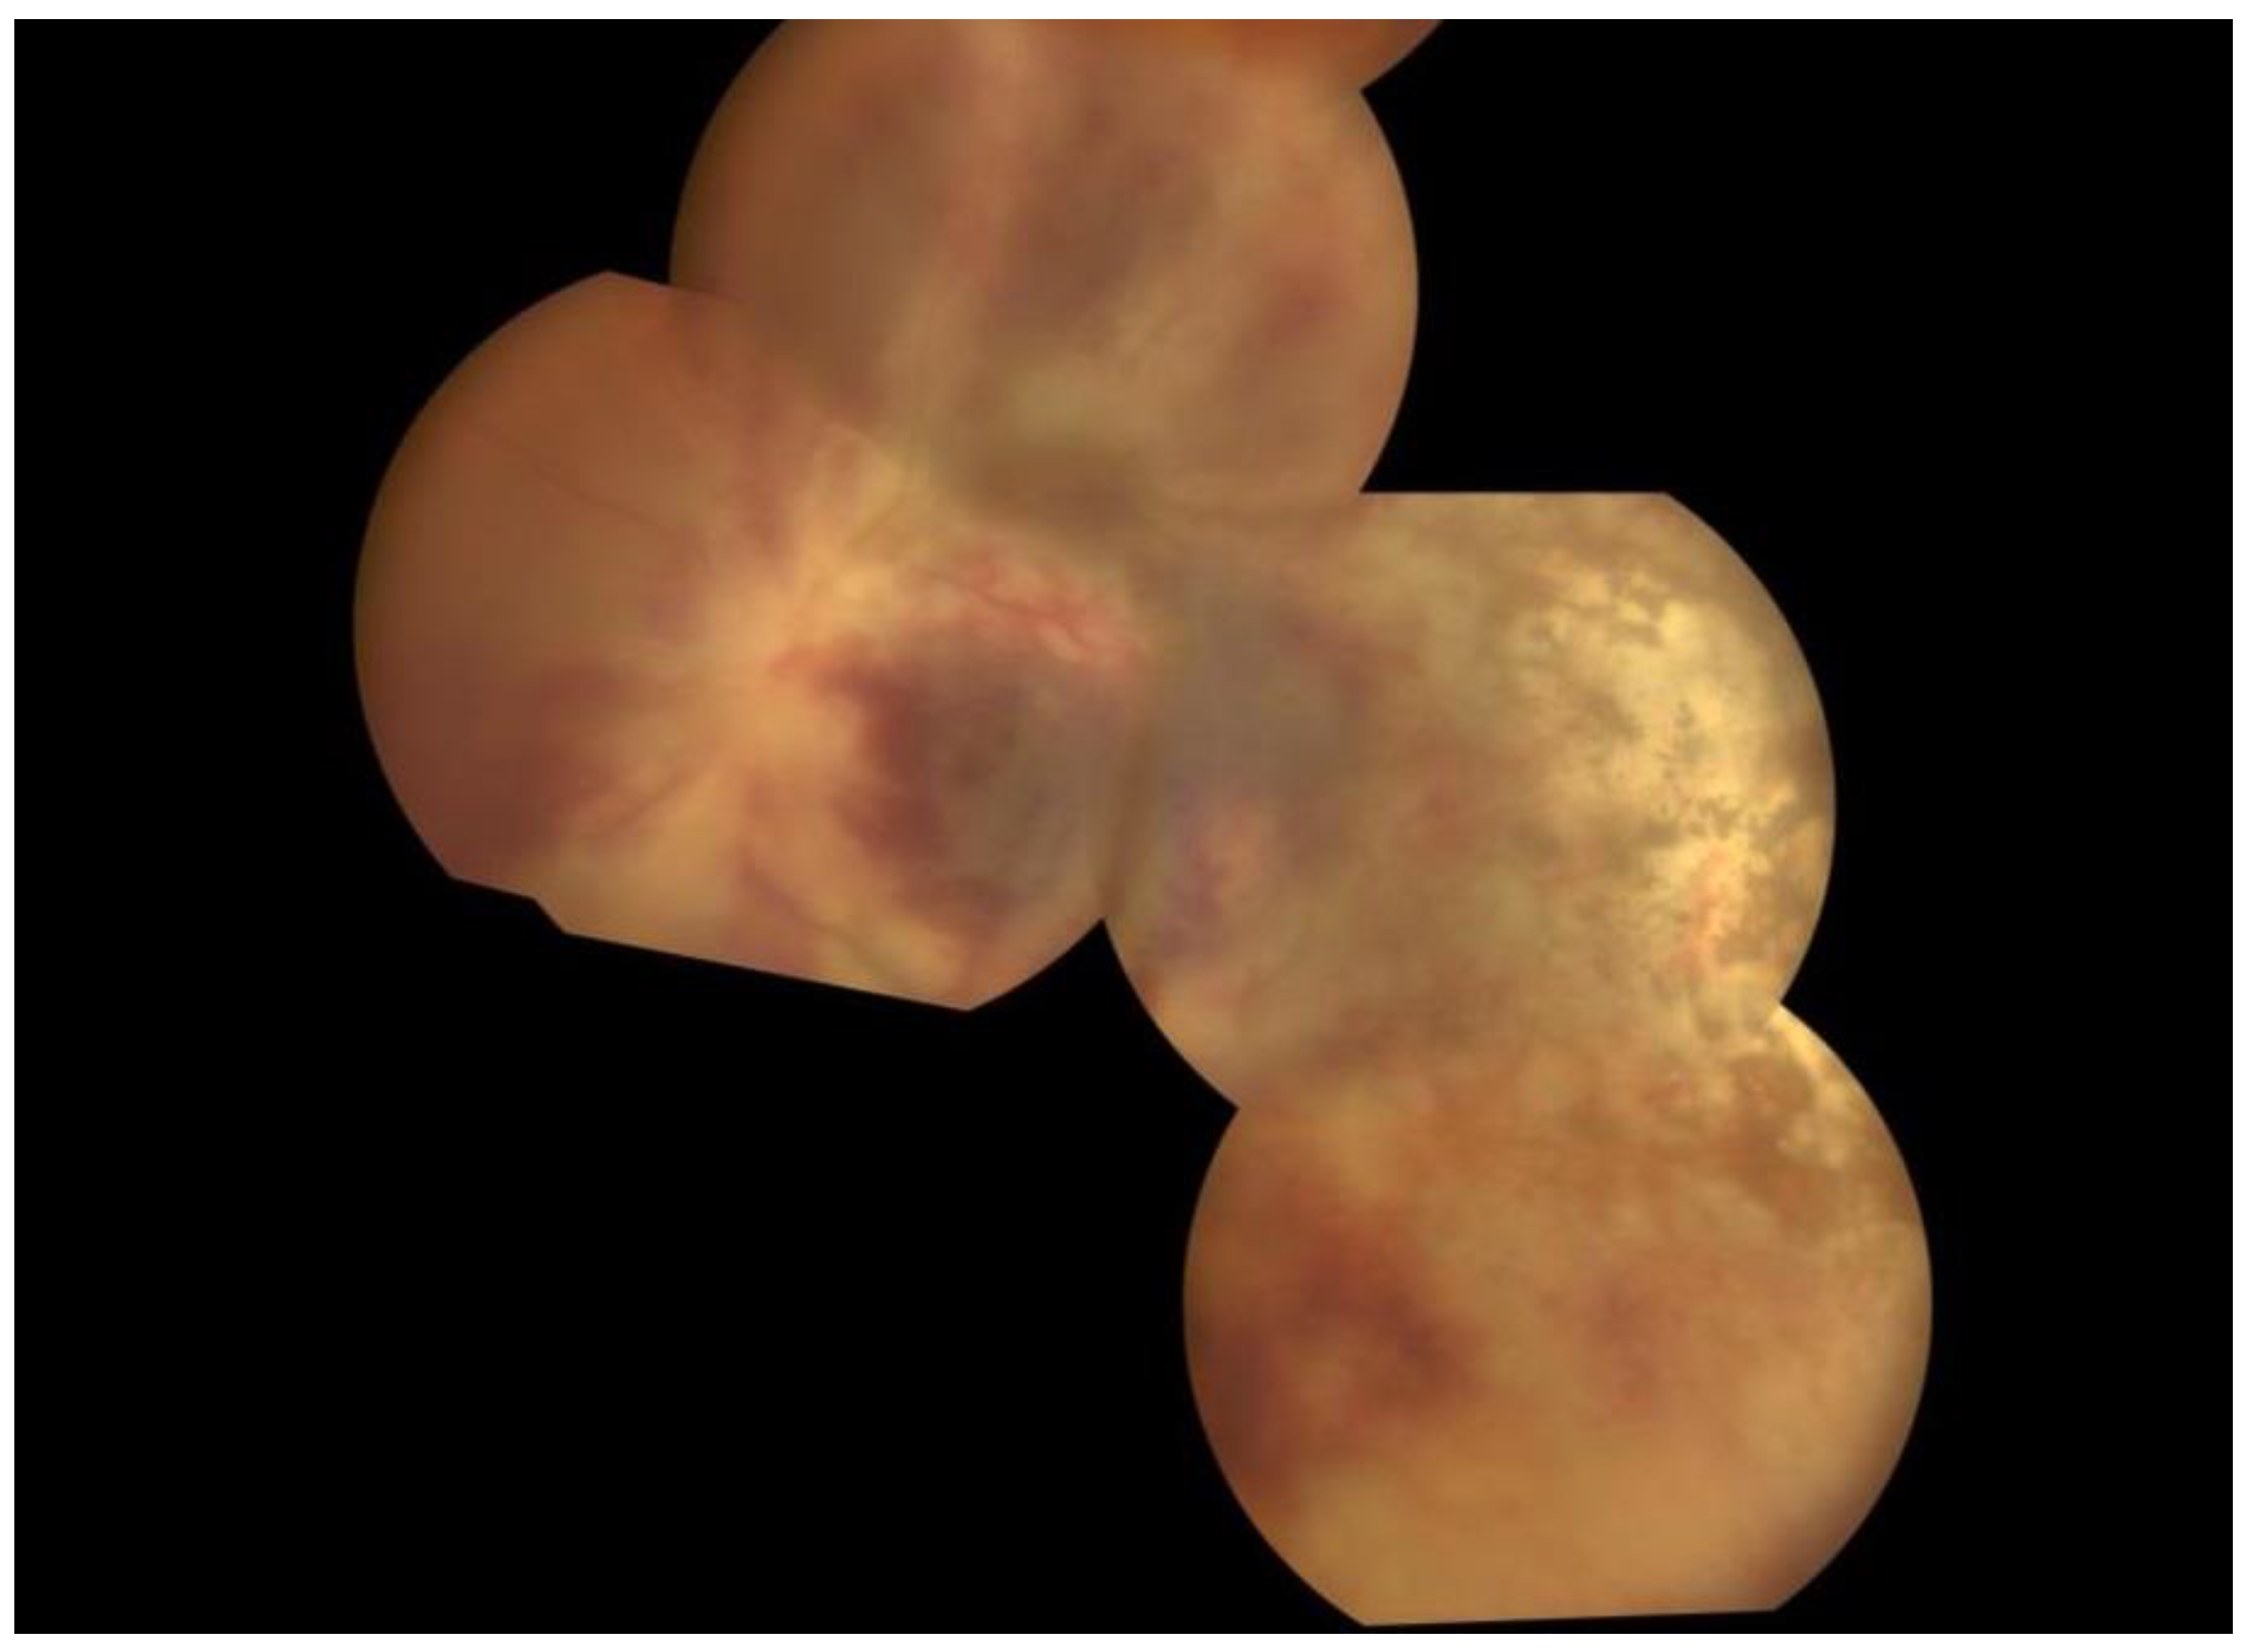

Eye examination at the end of induction therapy (one-month follow-up) showed the same visual status in the right eye and the worsening of the visual status in the left eye to complete blindness, know as no-light perception (NLP). Anterior chamber in both eyes showed no active inflammation as a sign of anterior uveitis, with no sequelae. Fundoscopy showed dramatic improvement in the retinal white zones (retinal pale areas) in the right eye, with remission of active inflammation. Meanwhile, the left eye showed pale ON (optic nerve), with moderate remission of active inflammation and hemorrhages (Figure 3).

Figure 3.

Wide-field fundus photographs of the left eye. One month after the first presentation, the left eye shows moderate remission of active inflammation and hemorrhages.